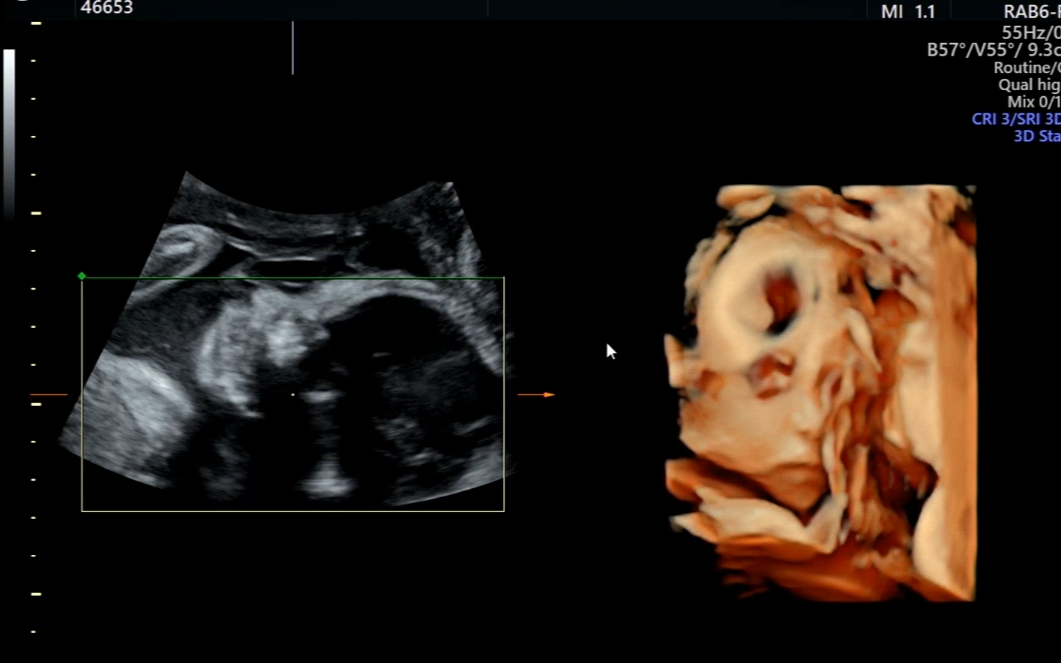

그런데 이번 28주 입체초음파는 완전히 달랐다.

“아, 이래서 다들 이 시기에 입체초음파를 보나 보다” 싶을 정도로

아가아가한 얼굴이 딱 나타났다.

손으로 턱 괴고 꿀떡이 등장!

입술 주변으로는 탯줄이 지나가고, 턱을 괴듯 손을 올리고 있어서 얼굴을 보기 쉽지 않았다.

배를 이리저리 흔들고 통통 친 결과 손을 조금 내려주었다.

놓치지 않고 바로 스캔하시는 초음파선생님.